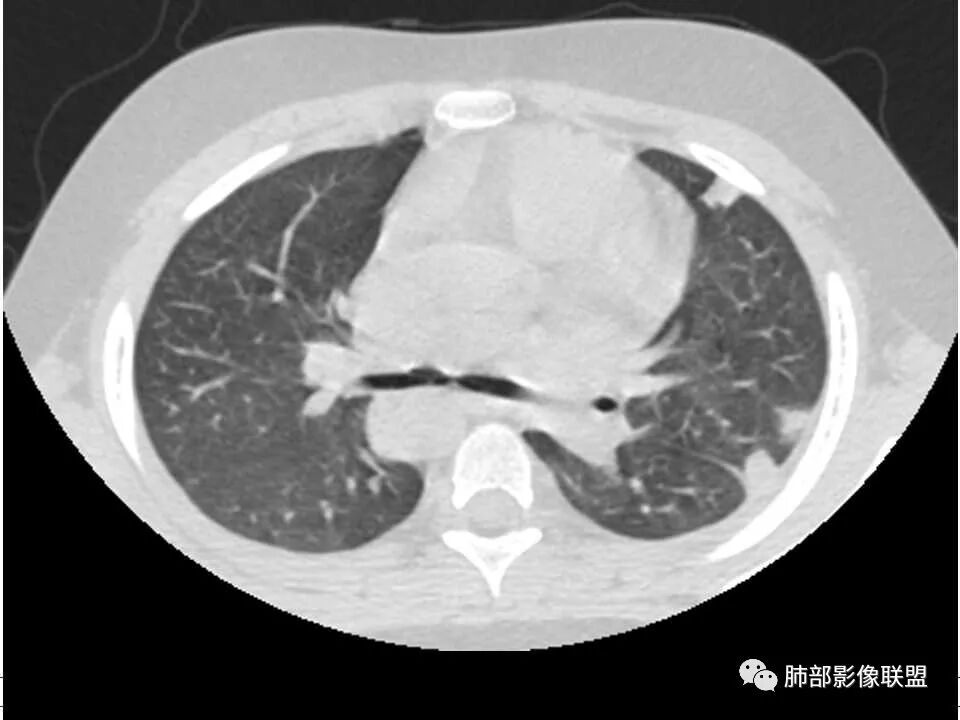

患者儿童,因右下肢疼痛伴肿胀14天就诊。病程中有发热及伴随症状。膝关节MRI提示右侧膝关节及右髌骨髁异常信号影,右膝髌上囊及关节腔内少量积液。胸部CT:双肺胸膜下多发结节影,部分结节空洞形成,且结节周围可见血管集束征。综合考虑血源性脓毒性肺栓塞、坏死性肺炎。右侧骨髓炎、血播性金葡菌肺炎,鉴别其他特殊感染及血管炎。

胸部ct:双肺多发空洞,结节,外带下叶为主,空洞内外光滑,有血管滋养征,综合病史及影像考虑脓毒性肺栓塞,结合病史,金葡可能性大。

小儿,急性起病,下肢疼痛,mr提示骨髓水肿,临床化验炎性指标高,考虑金葡菌骨髓炎,双肺多发结节,以血管支气管束及胸膜下分布为主,部分结节近端与血管相连,部分结节可见空腔,内壁光整,部分囊腔有张力,考虑骨髓炎并肺内血播感染,金葡?

2.双肺多发片影,随机分布,多空洞或囊腔,胸膜下多楔形影,气道未见受累等等符合脓毒血症影像学表现,尤其是金葡。

2、脓肿:实变区内脓肿,最常见吸入性金葡菌引起的多,下叶多见,在实变区中央,外壁不清,内壁光滑,可见气液平面;血源性脓肿,多发,结节状,大小无差异,边清,光滑,壁薄;

1. 多发胸膜下外周结节、< 3 cm 的楔形影和滋养血管征 CT 表现;

4.经恰当的抗生素治疗,肺部浸润影吸收。滋养血管征为一支血管影连接肺部周边病灶,在 2/3 以上患者出现,可作为高度提示 SPE 的征象。